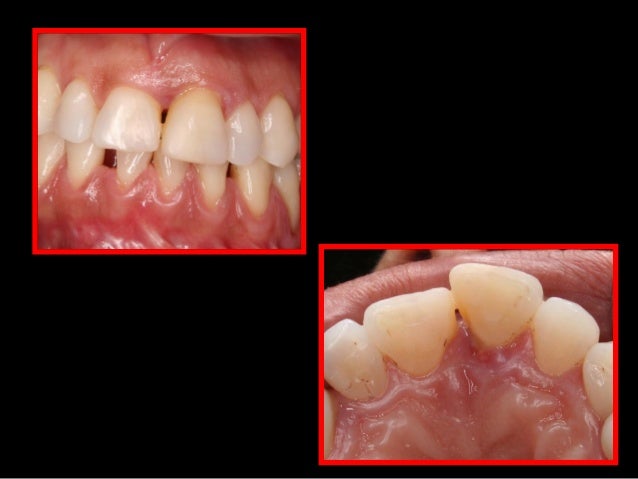

20. 20. Oclusão Patológica • Grande discrepâncias entre R.C. e M.I.H. • Presença de interferências originando os traumas oclusais . oclusais PEGORARO, et. al.; 2002

28. 28. Traumas Oclusais “Se origina através de uma relação de contato que interfere de alguma forma com a função ou parafunção. “ Classificação: Primário- Interferência Oclusal atuando sobre dentes com suporte periodontal sadio. Secundário- Interferência sobre dentes em periodonto comprometido em relação ao seu suporte ósseo. PEGORARO, et. al.; 2002

Em uma oclusão fisiológica ou orgânica, no final do fechamento mandibular, a ação dos músculos elevadores promove o assentamento dos côndilos nas fossas mandibulares do osso temporal, denominado posição de relação cêntrica (RC), coincidente com o máximo de contatos dentários posteriores bilateral, denominado máxima intercuspidação (MI) ou oclusão dentária. Como resultado a mandíbula assume posição estável denominada oclusão em relação cêntrica (ORC), na dimensão vertical de oclusão (DVO). Em seguida o relaxamento dos músculos elevadores gera a dimensão vertical de repouso (DVR).